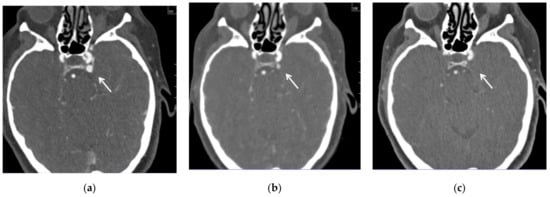

The follow-up CT angio examinations showed that the venous pouch of the CS-DAVF progressively decreased in size (Figure 5a–c), and at the final DSA after the end of the cycle of corticosteroid therapy (performed 7 months after discharge), it was completely occluded (Figure 6a–d). From the clinical point of view, the proptosis regressed, and diplopia and retroorbital pain disappeared; a slight conjunctival hyperemia remains but at three years, the patient is still free of symptoms.

Figure 5. CT angio on admission (a) and at 3 (b) and 6 (c) month follow-up. The venous pouch at the posterior aspect of the left cavernous sinus (white arrow) progressively decreased in size and disappeared.